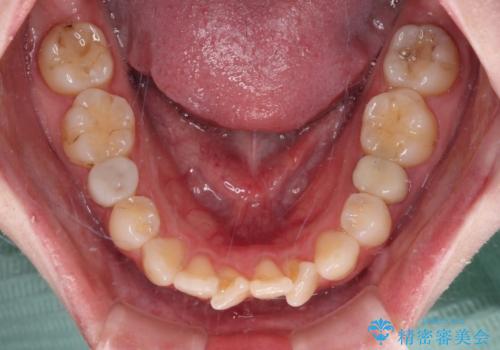

開咬と前方に飛び出した前歯 インビザラインによる矯正治療

- 上下前歯の非接触と叢生を気にして来院された患者様です。

開咬の改善はインビザラインの最も得意とするところであるため、インビザラインを用いて矯正治療を行うこととしました。

舌の突出癖改善のトレーニングをしっかりと行っていただき、上下前歯が接触する咬み合わせを達成することができました。